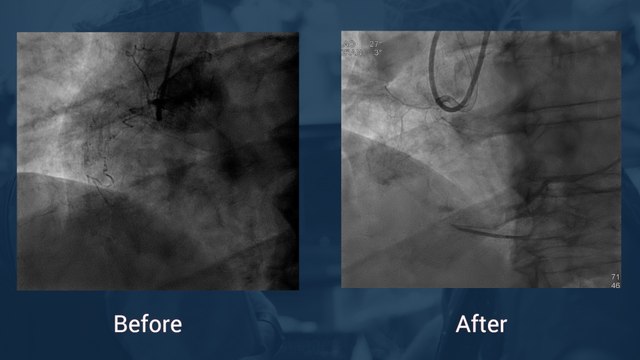

Tortuous and calcified ostial RCA CTO

Uploaded: December 15, 2017 Views: 24